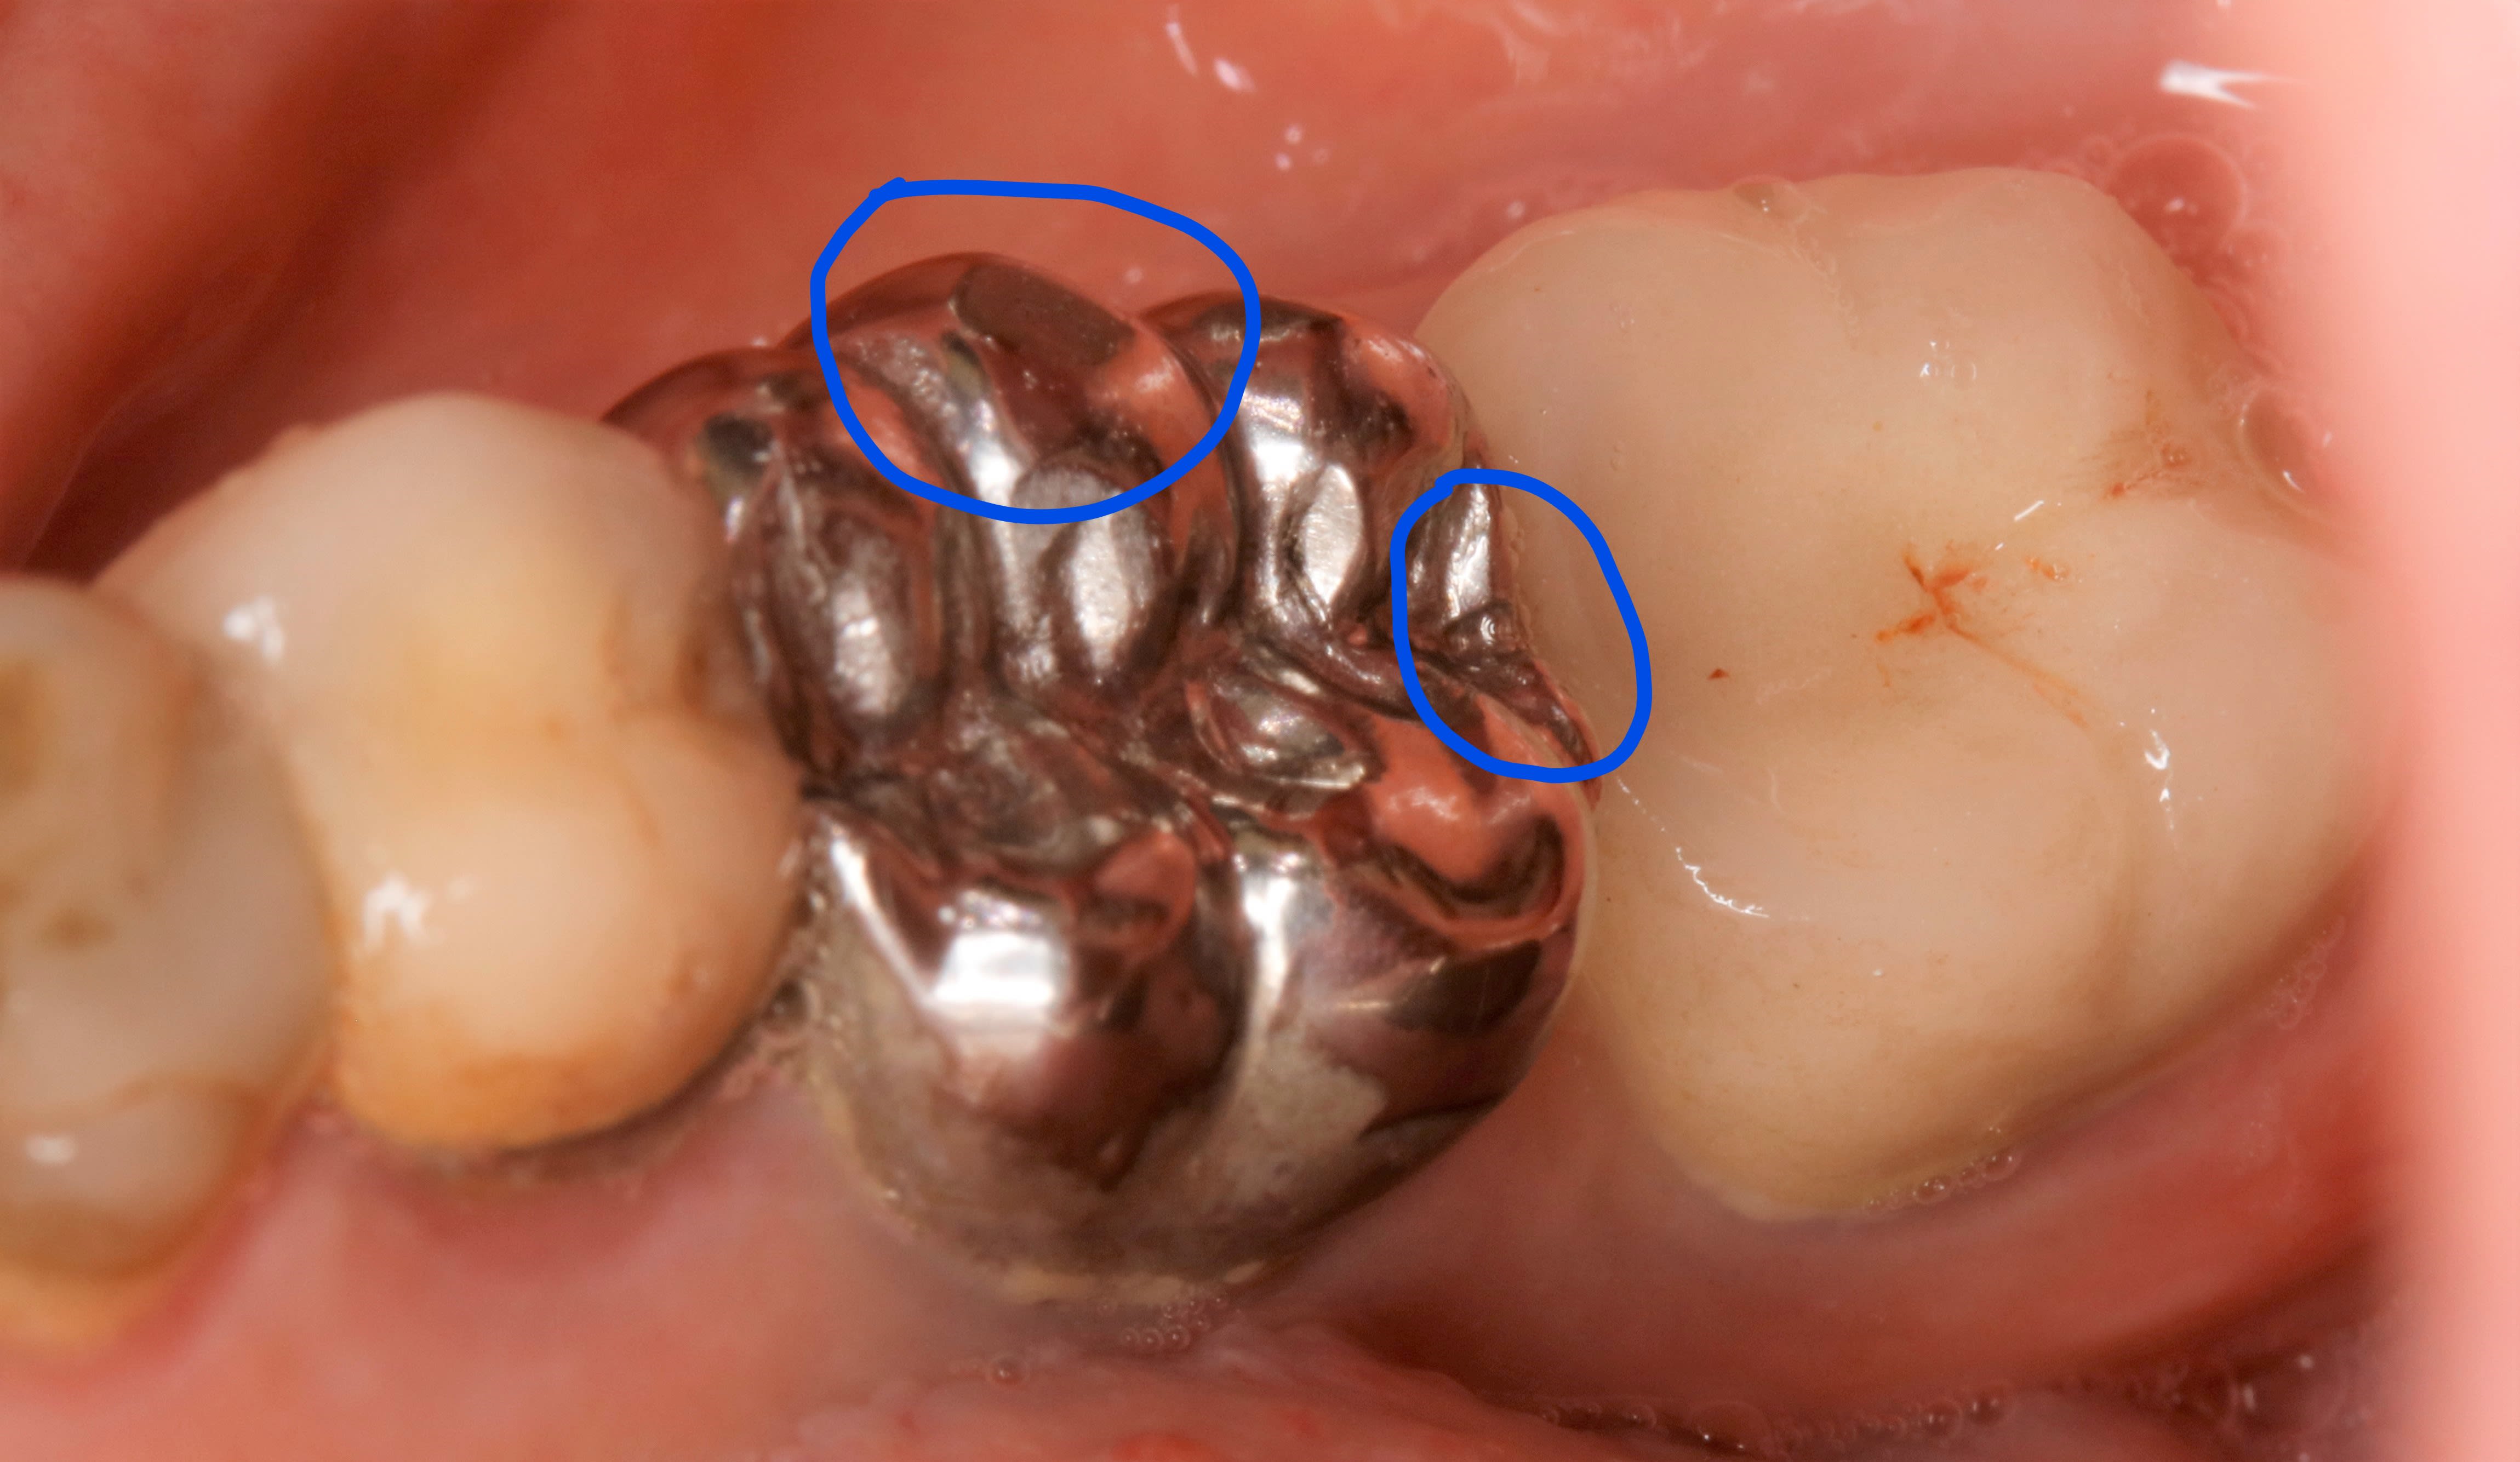

ça ce n en est pas forcement

Inked mg 1644   copie li mppray - Eugenol